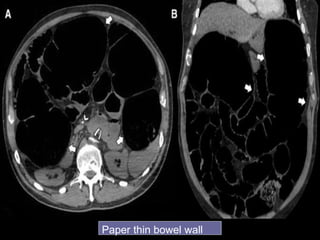

 Thinned bowel wall with poor or absent

enhancement

Paper thin bowel wall

White attenuation Grey attenuation

Water target sign Pneumatosis intestinalis